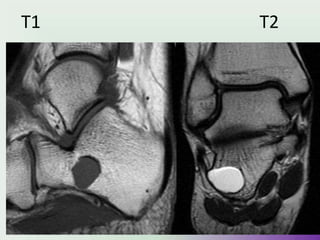

• MRI

• MRI is useful in evaluating for soft tissue extension and for

confirming the diagnosis.

• Enchondromas appear as well circumscribed somewhat

lobulated masses replacing marrow.

• T1

Intermediate to low signal

• T1 C+ (Gd)

enhancement is variable, and may be seen both peripherally or

of translesional septae. Similar pattern of enhancement may be

seen in chondrosarcomas.

• T2

Typically of background intense high signal

MRI

STIR

• Hypointense

T2

Hyperintense

UMY